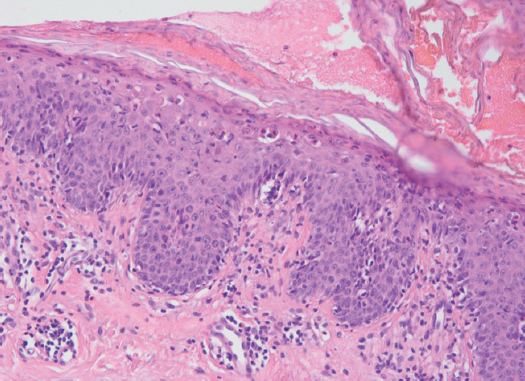

Erythroderma – the term used for the description intensive and usually widespread reddening of the skin which has arisen owing to activation of the previous inflammatory dermatosis. Among the causes of erythroderma are the progression of chronic dermatoses, refractory to therapy, medication or inadequate local treatment of dermatoses. In addition, it can be a symptom and/or a sign of systemic diseases (lymphoma, leukemia, tumors of the lungs, intestines and ovaries). Most of the cases of erythroderma described in the literature were induced by taking different types of drugs and dietary supplements. High lethality of this category of patients is associated with both the main disease that caused the development of erythroderma and the nature of emerging metabolic disorders. Erythroderma is one of the most severe conditions that threaten the life of the patient, requiring special approaches in the diagnosis and early treatment. When diagnosing and determining the forms of erythroderma, one of the determining factors is clinical examination and clinical and pathological correlation. Patients with diseases of a digestive tract have high risk of development of side effects from intake of drugs and carrying out tool methods of a research. One of the screening methods of a research is the fibrogastroduodenoskopy (EGD). We provide the description of the first case in our practice of the patient with the erythroderma which has arisen after the EGD-research. Questions of pathogenesis, differential diagnostics of an erythroderma on the basis of a clinical picture and histological signs with illustrations are also discussed.